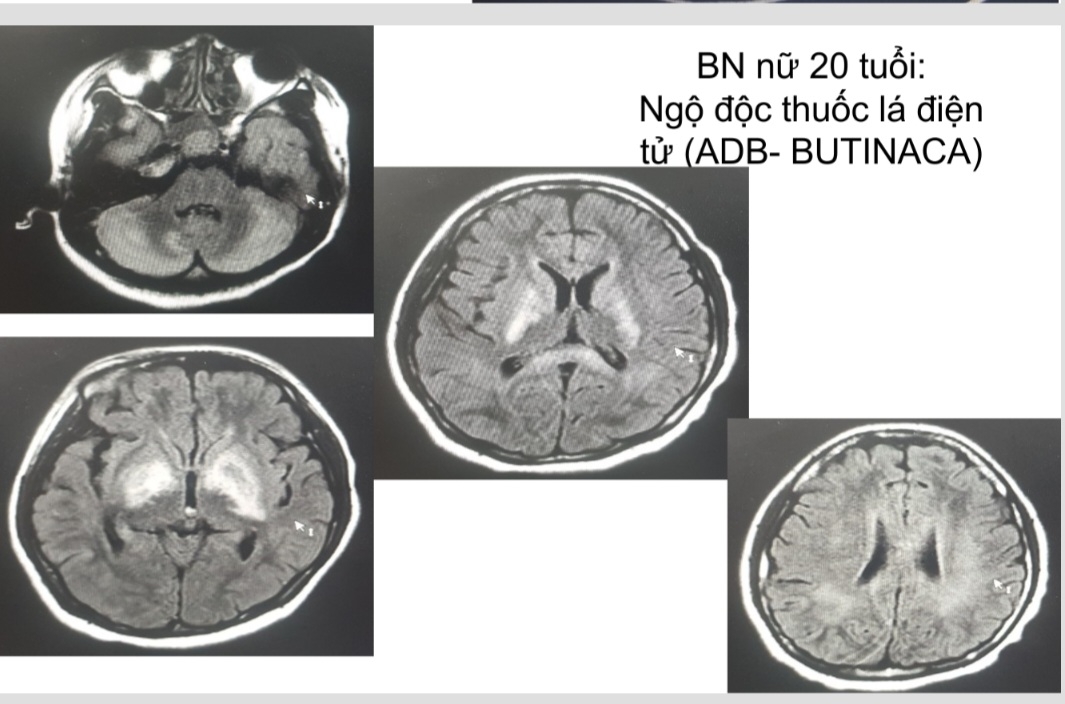

Hình ảnh não bệnh nhân bị tổn thương nặng do thuốc lá điện tử

Bác sĩ Nguyên cho biết: Ngày nào Trung tâm Chống độc cũng có bệnh nhân ngộ độc thuốc lá điện tử được điều trị tại đơn vị, trong đó rất nhiều trường hợp là học sinh, thanh thiếu niên phải cấp cứu do ngộ độc chất ma túy trộn thuốc lá điện tử. Các ca ngộ độc thuốc lá điện tử đều vào viện với biểu hiện co giật, kích thích, vật vã, ảo giác, loạn thần, hôn mê, tổn thương não và nhiều cơ quan khác, để lại di chứng nặng nề với sức khỏe.

Hiện Trung tâm Chống độc đang điều trị cho 2 bệnh nhân trẻ (một bệnh nhân 23 tuổi và một bệnh nhân 29 tuổi) đều bị ngộ độc nặng sau khi sử dụng thuốc lá điện tử. Bệnh nhân T.Q.T (23 tuổi, ở Thường Tín, Hà Nội) có tiền sử hút thuốc lá điện tử 2 năm nay. Theo lời kể của người nhà, tối ngày 1/12 bệnh nhân có dùng thuốc lá điện tử được cho thêm “thử” hương liệu mới (do shipper giới thiệu), đến 5 giờ sáng ngày hôm sau bệnh nhân lên cơn co giật, sùi bọt mép, co giật toàn thân. Bệnh nhân được đưa đi cấp cứu ở Bệnh viện tuyến trước nhưng không đỡ, sau đó được chuyển đến Trung tâm Chống độc vào ngày 9/12. Xét nghiệm mẫu thuốc lá điện tử bệnh nhân mang đến phát hiện chất ma túy cần sa tổng hợp là ADB-Butinaca.